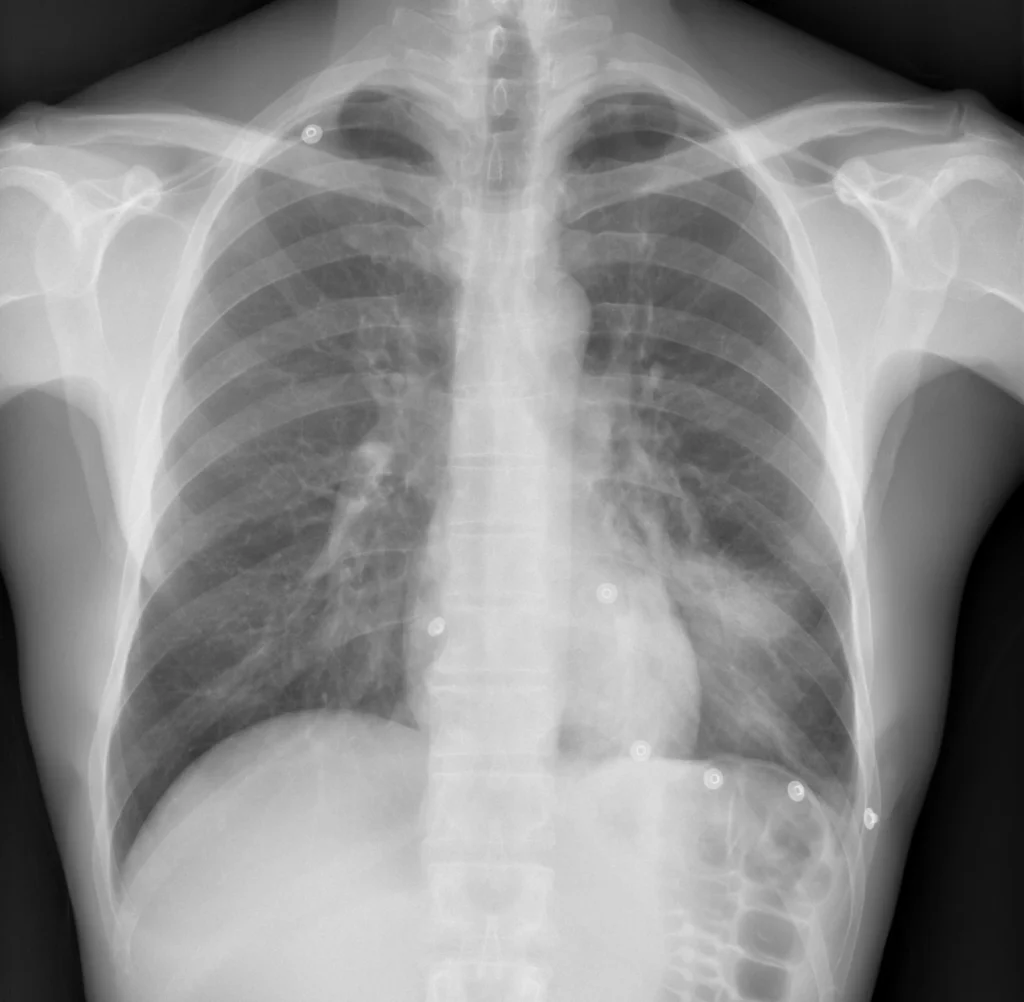

Rx de tórax PA. Aumento de la densidad en el sector inferior del pulmón izquierdo, por ocupación del espacio aéreo. El borde izquierdo del corazón se puede ver claramente. En el tercio inferior del hemitórax izquierdo, se observan las imágenes de alta densidad que corresponden a electrodos posicionados para el ECG.

Opacidad del parénquima pulmonar con broncograma aéreo, en la proyección PA se observa en el tercio inferior del pulmón, en la proyección lateral ocupa el sector posteroinferior.

El borde cardíaco está bien definido (signo de la silueta negativo), lo que indica que la localización de la condensación es posterior, por lo tanto, en segmentos basales del lóbulo inferior izquierdo.